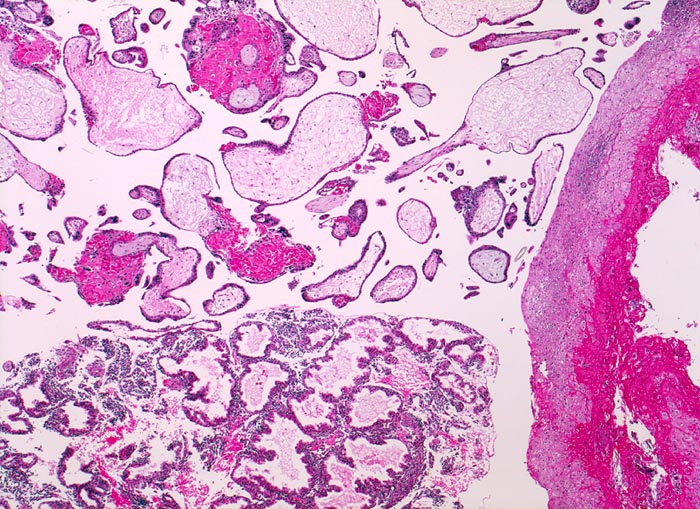

Chromosomenaberrationen verursachen nicht nur beim Feten, sondern auch an der Chorionzotte morphologisch fassbare Entwicklungsstörungen: mangelnde Verzweigungen, wandernde Trophoblastzellen im Stroma, mangelhafte Vaskularisation, hydropische Alteration des Stromas und herdförmige Atrophie oder auch Hyperplasie des Trophoblasten sind typische Befunde bei einer Chromosomenaberration. Aborte mit Triploidie zeigen in der grossen Mehrzahl das Bild einer Partialmole. Eine Tetraploidie kann das Bild einer Windmole (=Windei), einer Embryonalmole oder seltener einer Partialmole verursachen. Autosomale Trisomien können ebenfalls als Windmole oder als Embryonalmole imponieren. In nur etwa 25% aller Spontanaborte sind bei der pathomorphologischen Untersuchung ein Embryo, Embryofragmente oder ein Nabelschnuranteil nachweisbar. Die morphologische Untersuchung des Abortmaterials stellt eine wichtige Ergänzung zu den klinischen Befunden dar.

• Vergrösserte Plazentarzotten mit hydropischem Zottenstroma.

• Vereinzelt Zytotrophoblasteinschlüsse im Stroma.

• Vorwiegend einschichtiges Zytotrophoblastepithel ohne Atypien und mehrkerniger Synzytiotrophoblast. Physiologische polare Trophoblastproliferate.